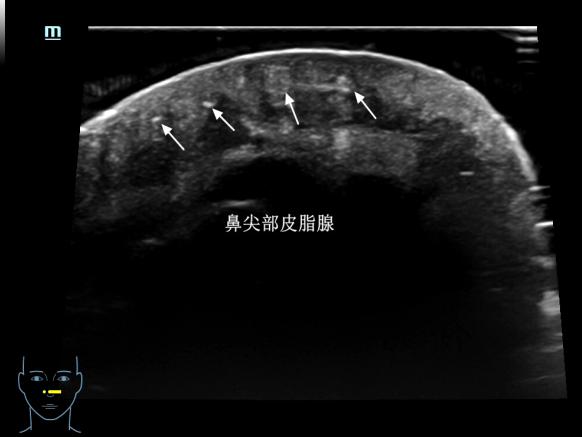

我们的皮肤从外到内分为表皮、真皮、皮下组织三层,就像一层薄外套裹着两层“保暖层”。在超高频探头下,薄薄的皮肤可以变成一张 “皮肤剖面图” ,不仅可以看到表皮、真皮、皮下组织的结构,精确测量其厚度,还可以清晰显示其内的毛发、毛囊、皮脂腺等肉眼及普通超声无法识别的结构。